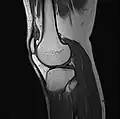

MRI

Both anterior cruciate ligament (ACL) and posterior cruciate ligaments (PCL) are hypointense on both T1 and T2 weighted images of MRI. However, some high signal striations are often seen at the distal part of the ACL, making ACL higher intensity than PCL on MRI scans.[20]